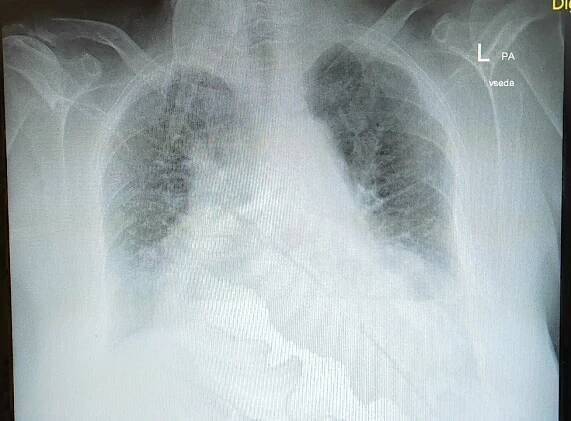

Plicní embolie je ucpání krevního řečiště plic vmetkem (embolus), nejčastěji z dolní končetiny. Projeví se náhlou dušností, bolestí na hrudi, kašlem až vykašláváním krve.

Při plicní embolii dochází k částečnému nebo úplnému ucpání plicní tepny nebo některé z jejich větví. Nejčastěji je to způsobeno krevní sraženinou, která se ...

Plicní embolie je ucpání krevního řečiště plic vmetkem (embolus), nejčastěji z dolní končetiny. Projeví se náhlou dušností, bolestí na hrudi, kašlem až vykašláváním krve. Postihne-li rozsáhlou oblast plic, dochází k poklesu krevního tlaku, šoku a následné smrti. Na tuto nemoc zemřel známý český herec a komik Vlasta Burian, ovšem jeho embolii předcházel prodělaný a nedoléčený zápal plic. Naddiagnostikování bývá časté. Wikipedie